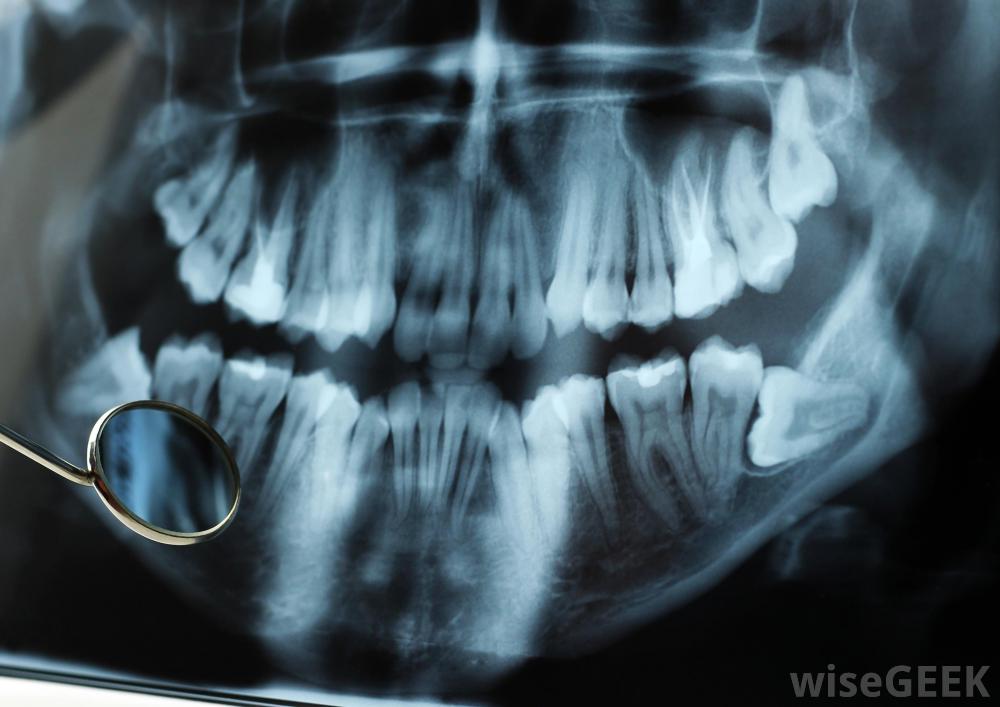

口腔放射学是一门医学专业,专注于口腔和周围区域的诊断图像的创建和解释。牙医在他们的实践中使用口腔放射学,头颈部外科医生、颌面外科医师和其他在头颈部工作的医学专业人员也一样。在某些地区,口腔放射学是一个公认的医学子专业,牙医和放射科医生等可以申请该领域的委员会认证。委员会认证表明该领域的高水平能力以及对卓越的承诺

口腔放射科由肿瘤学家监督。许多医学成像技术可用于口腔、牙齿、颌骨和颈部的研究。这些技术包括超声成像,x射线成像、磁共振成像(MRI)、计算机断层扫描(CT)等等。口腔放射科医生研究所有这些成像技术,熟悉它们的工作原理和使用方法。这包括在辐射物理方面有一个全面的基础,以便口腔放射科医生熟悉辐射暴露及其控制方法。

口腔放射学允许牙医和口腔外科医生创建和读取口腔的诊断图像一个训练有素的牙医或放射科医生通常可以为头部和颈部区域拍摄高质量的图像,但有时需要口腔放射科医生来处理具有挑战性的病例。这些医学专家也可以参与图像的解释。熟悉数千个病例的口腔放射学专家甚至可以发现和解释模糊的标记可能对病人的情况有重要的了解。这些医学专家可以评估异常情况,识别问题,向医疗团队的其他成员提出治疗建议,并参与后续护理,以确认某个程序对患者有效。他们也可能参与对高危人群的持续监测,进行影像学研究以确定新出现的问题。放射学不应与放射治疗混淆。两者都涉及放射治疗,但方式不同。在放射治疗中,治疗剂量的辐射是为了医疗目的而对病人进行的。头部和颈部的放射治疗通常是在癌症治疗中进行的,由头颈部肿瘤学家或普通肿瘤学家监督,而不是由口腔放射科医生、利用辐射进行成像的专家监督,不是治疗。一个相关的领域,介入放射学,涉及使用影像学来指导医疗程序,例如放置导管。口腔放射科的专家也可以获得介入放射学的认证,并可以执行像血管造影这样的程序,利用示踪染料和医学影像学研究血管系统。